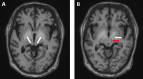

Patients with chronic liver disease (CLD) are prone to complications associated with impaired liver functioning. This coupled with iron-deficiency anaemia (IDA) can predispose them to multiple comorbidities. We present an interesting case of a 69-year-old woman with a background history of liver cirrhosis due to metabolic dysfunction-associated steatotic liver disease (MASLD) with frequent travels to Bangladesh, a southeast Asian country known for having high levels of manganese (Mn) in water for domestic use. She presented with progressively worsening cognition and extrapyramidal symptoms. She underwent routine blood tests including for liver functions followed by a non-contrast computed tomogram (CT) of the head that did not suggest a possible cause. However, magnetic resonance imaging (MRI) of the brain showed hyperintensities bilaterally in the globus pallidus, subthalamic nucleus, red nucleus, and substantia nigra and raised the possibility of Mn toxicity. This was confirmed with repeated raised blood levels of Mn. The query was raised for acute toxicity to Mn, followed by consideration of CLD history associated with reduced elimination of Mn. This was complicated further by her history of IDA. Her case was discussed in a multi-disciplinary setting with specialities including radiology, gastroenterology, neurology, psychiatry, hepatology, and elderly medicine. Following this, a decision was made for the best supportive management of the patient. This case highlights the importance of MRI in the detection of a rare case of Mn toxicity, in a predisposed individual contributing to cognitive decline with extrapyramidal symptoms.